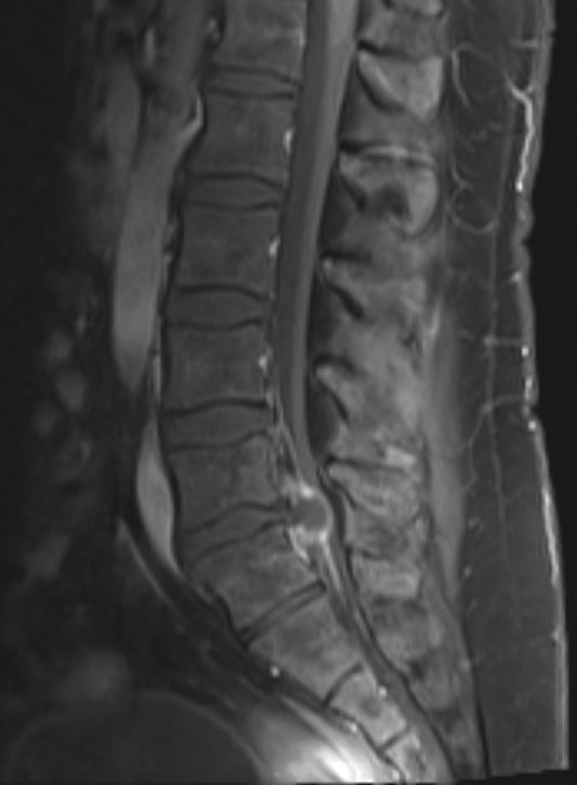

A 37 yo male with chronic low back pain presents with acutely worsening low back pain and ambulatory dysfunction. Patient reports being unable to walk due to severity of back pain over the last 2-3 days. Denies any red flag symptoms such as saddle anesthesia, fevers, cancer history, bowel or bladder incontinence, or IV drug use. Further history and physical exam are difficult to obtain due to the patient's significant discomfort and unwillingness to participate. Lumbar spine MRI shown below. What's the diagnosis? Scroll down for answer.

Answer: L5/S1 disc herniation

Radiology read of MRI:

1. Large peripherally enhancing left posterior paracentral structure at L5-S1 compressing

the descending left S1 nerve root and severely compressing the spinal canal and cauda equina nerve roots. This most likely represents a large disc extrusion rather

than an abscess.

2. Epidural lipomatosis congenitally narrowing the lumbar spinal canal, particularly at L5-S1, nearly completely effacing the sacral spinal canal.